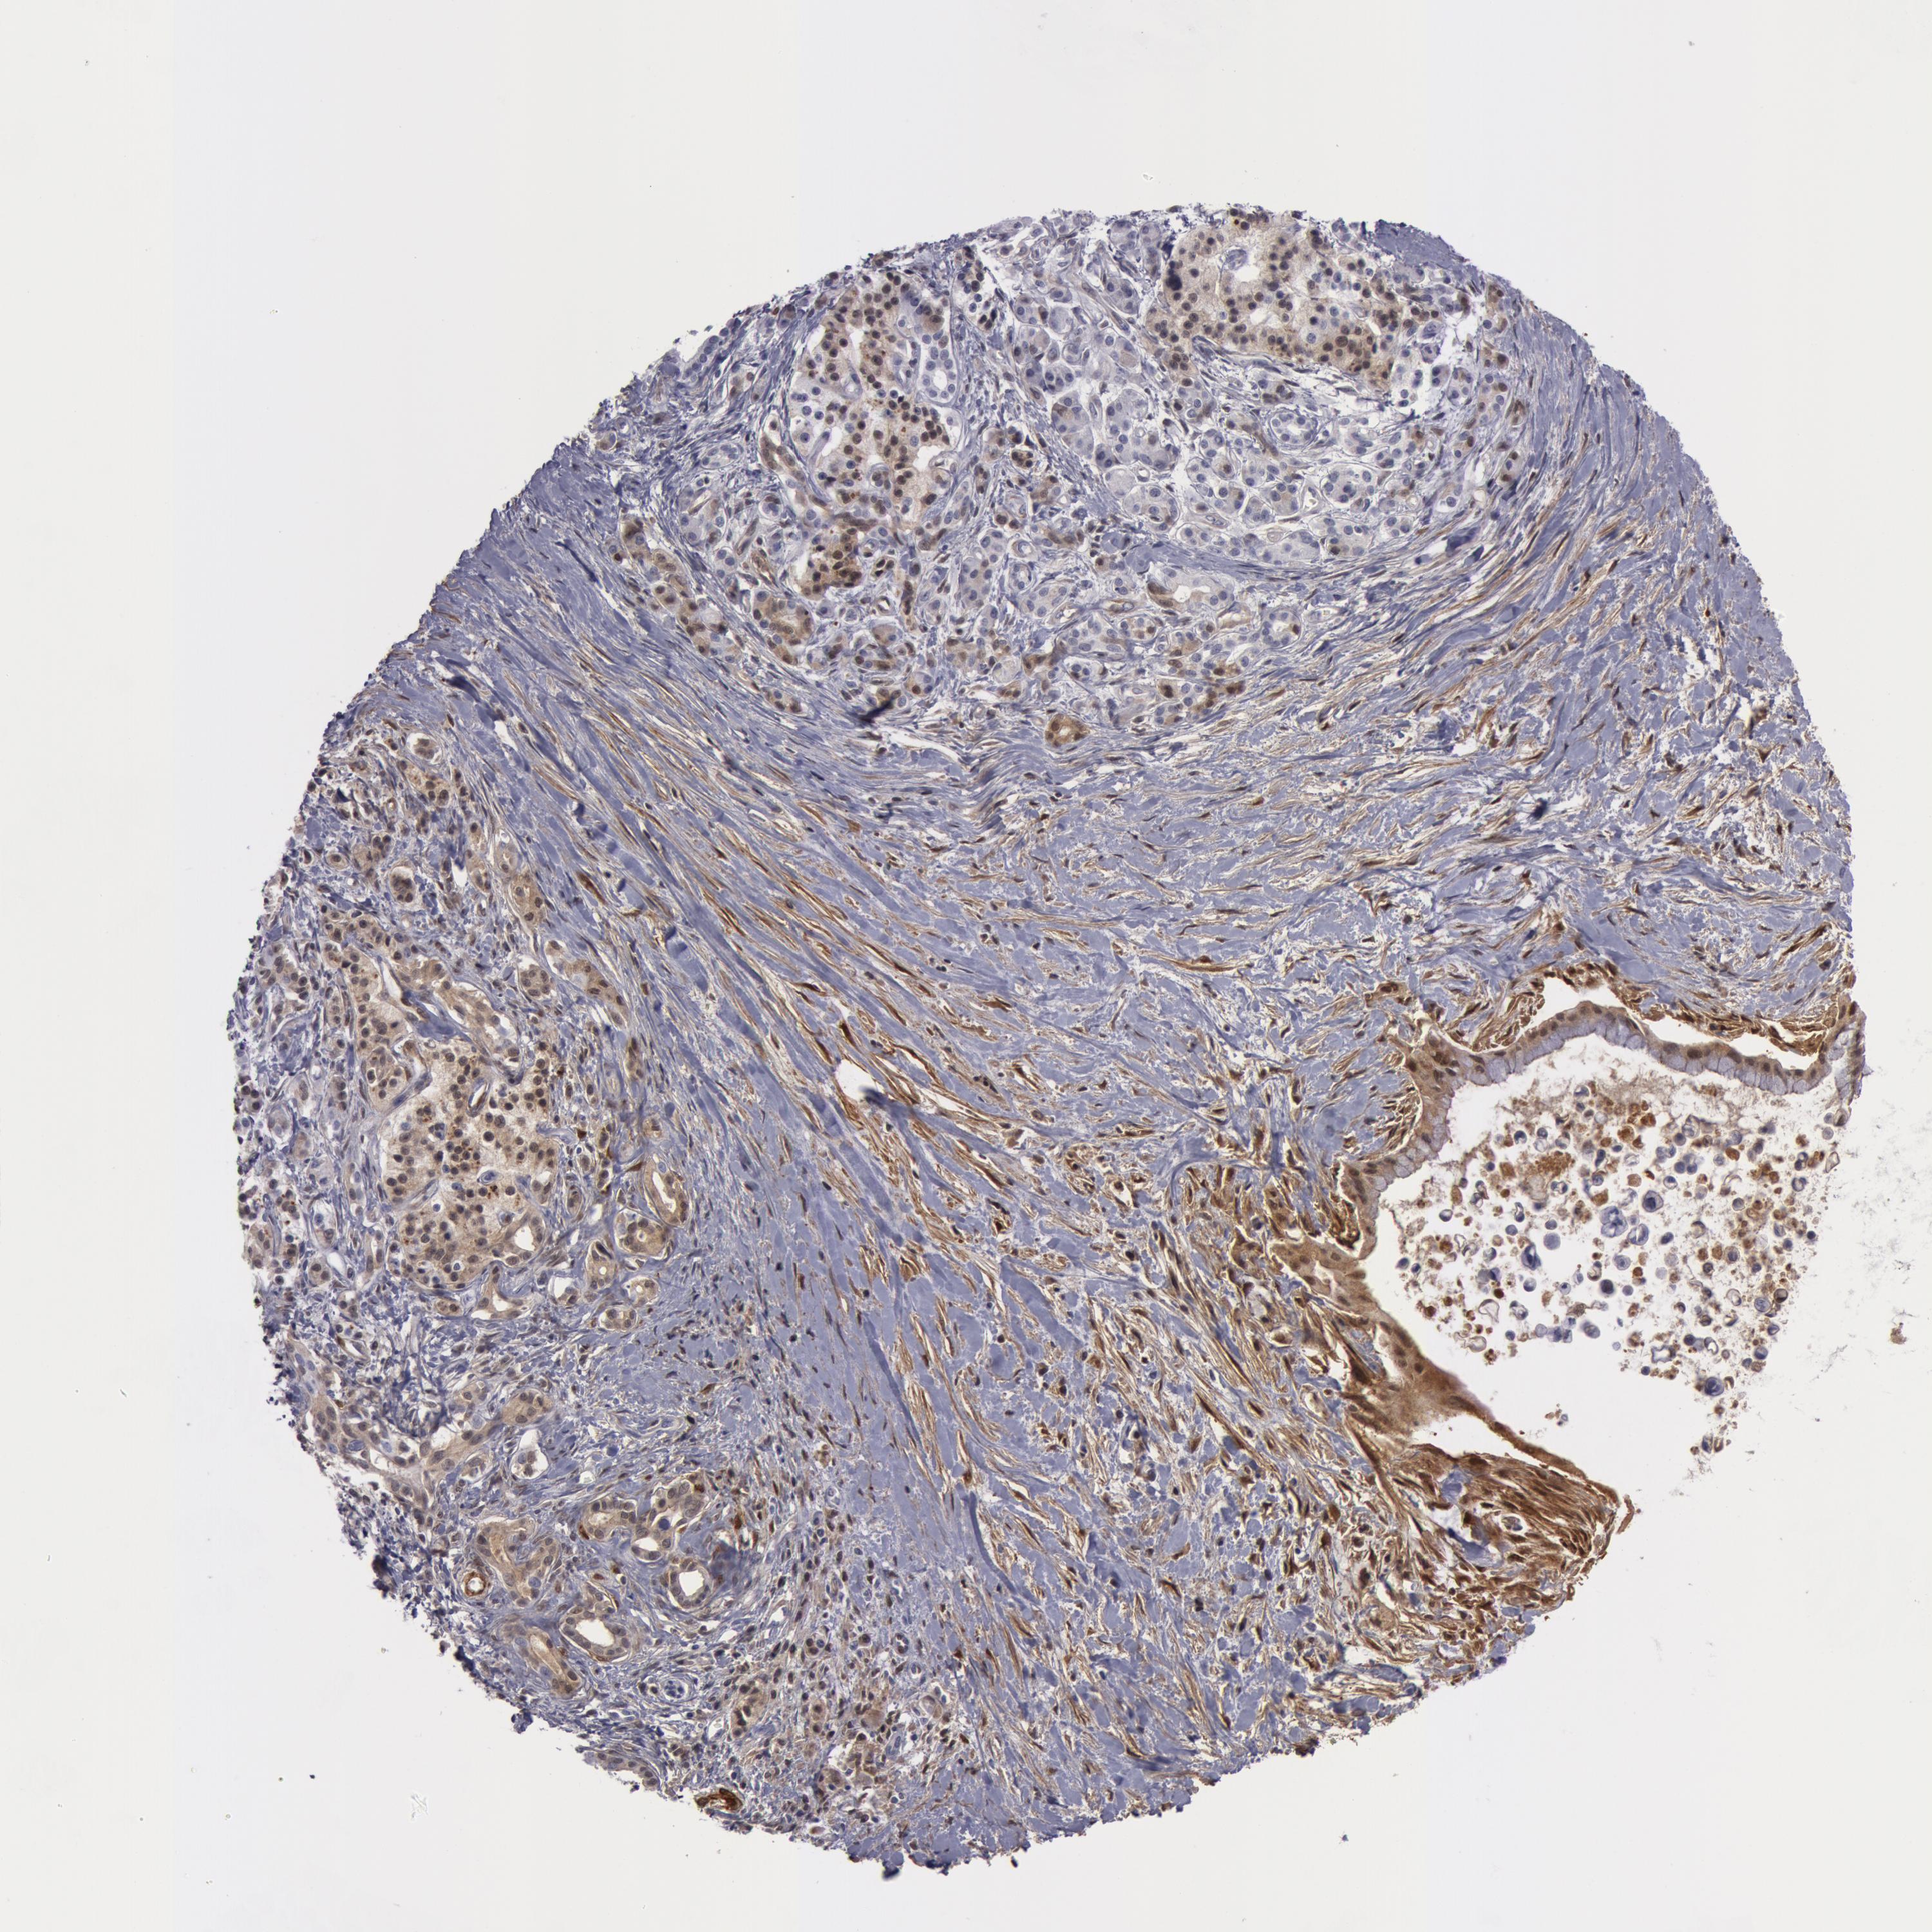

PANCREATIC CANCER - Protein expressioni

A mouse-over function shows sample information and annotation data. Click on an image to view it in a full screen mode. Samples can be filtered based on level of antibody staining by selecting one or several of the following categories: high, medium, low and not detected. The assay and annotation is described here.

Note that samples used for immunohistochemistry by the Human Protein Atlas do not correspond to samples in the TCGA dataset.

Antibody stainingi

Antibody staining in the annotated cell types in the current human tissue is reported as not detected, low, medium, or high, based on conventional immunohistochemistry profiling in selected tissues. This score is based on the combination of the staining intensity and fraction of stained cells.

Each image is clickable and will lead to virtual microscopy that enables deeper exploration of all samples and also displays staining intensity scores, fraction scores and subcellular localization as well as patient and tissue information for each sample.

Antibody HPA019467

Antibody HPA061657

Antibody CAB001447

Staining

High

Medium

Low

Not detected

Intensity

Strong

Moderate

Weak

Negative

Quantity

>75%

75%-25%

<25%

None

Location

Nuclear

Cytoplasmic/membranous

Cytoplasmic/membranous,nuclear

Adenocarcinoma, NOS